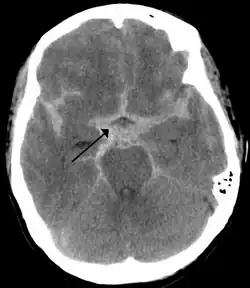

Subarachnoid hemorrhage as shown on a CT scan. It is denoted by the arrow. This type of injury may result in damage to the brainstem, which could initiate or worsen the symptoms of the Cushing reflex

As first postulated by Harvey Cushing, raised intracranial pressure is the primary cause of the Cushing reflex.[3] Furthermore, continued moderate increases in cranial pressure allows for the Cushing reflex to occur. In contrast, rapid and dramatic pressure rises do not allow for the mechanism of the reflex to sufficiently take place.[12] Elevated intracranial pressure can result from numerous pathways of brain impairment, including: subarachnoid hemorrhages, ischemia, meningitis, trauma, including concussions, hypoxia, tumors, and stroke. In one study, it was confirmed that raised ICP due to subarachnoid hemorrhaging causes mechanical distortion of the brainstem, specifically the medulla. Due to the mechanism of the Cushing reflex, brainstem distortion is then swiftly followed by sympathetic nervous system over activity.[13] In addition, during typical neurosurgical procedures on patients, especially those involving neuroendoscopic techniques, frequent washing of the ventricles have been known to cause high intracranial pressure.[7] The Cushing reflex can also result from low CPP, specifically below 15 mmHg.[14] CPP normally falls between 70-90 mmHg in an adult human, and 60-90 mmHg in children.